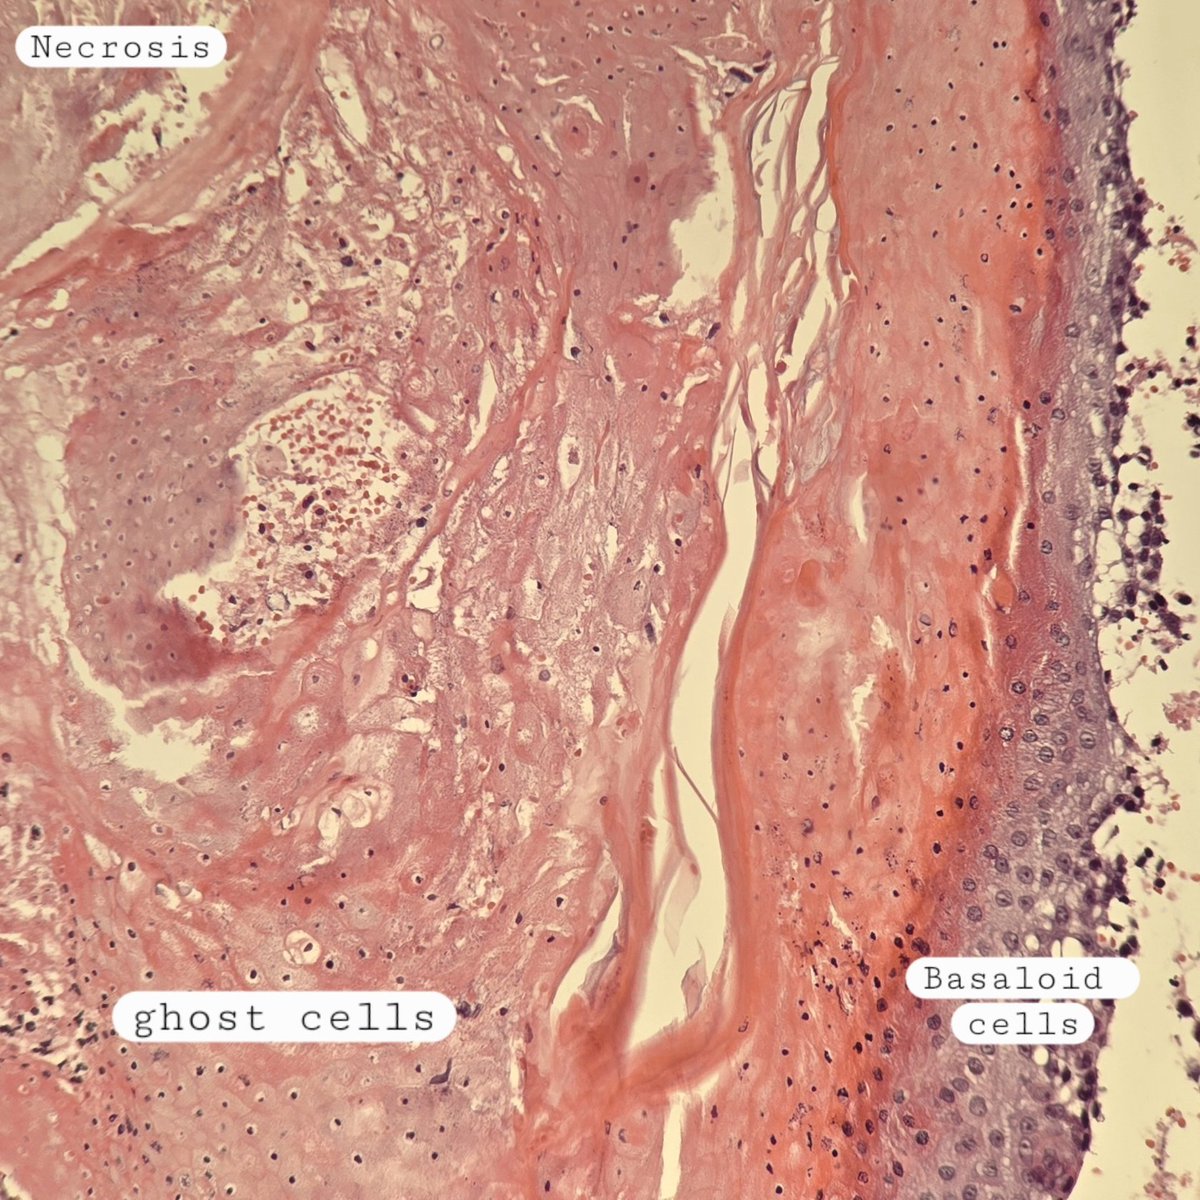

#backtobasics Pilomatrixoma 🔬 ✔️Benign skin adnexal tumor ✔️basaloid proliferation resembling the hair matrix cells, which matures into structureless eosinophilic cells lacking nuclei called shadow/ghost cells ✔️Frequently there are areas of calcification #xpath #dermpath